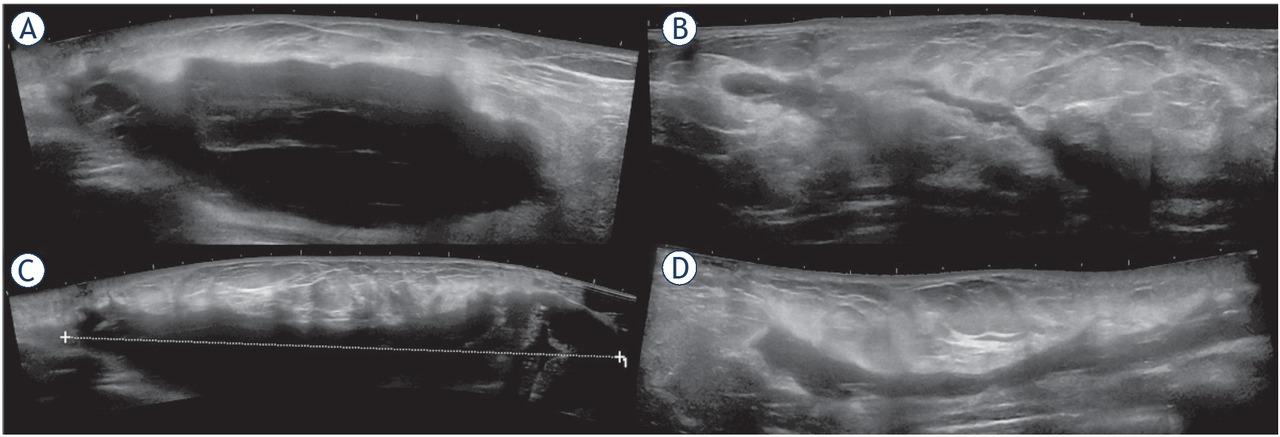

Figure 2